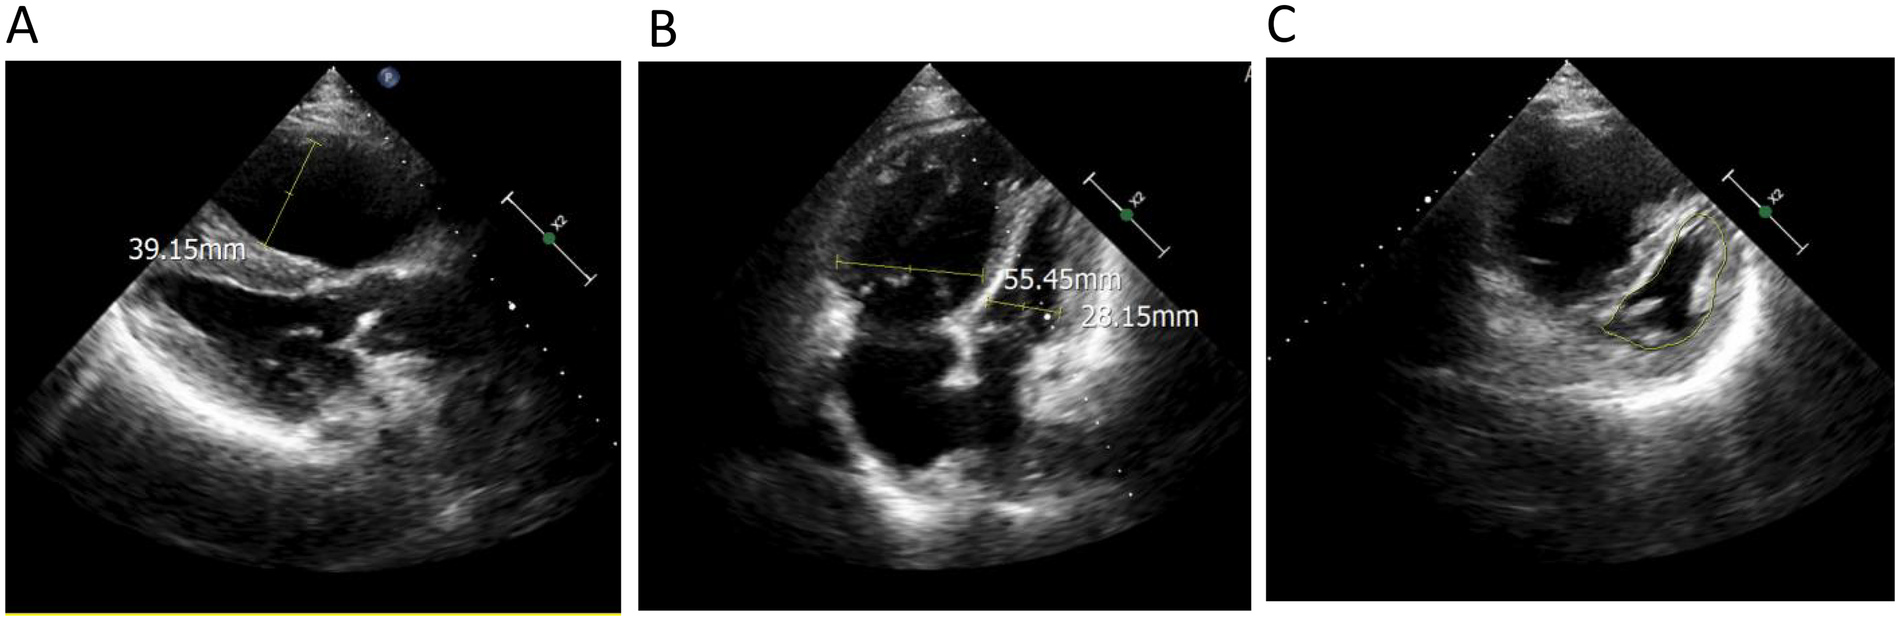

Femoral arterial blood gas analysis showed PaO2 49.7ā mm Hg, PaCO2 28.4ā mm Hg, oxygen saturation 86.6%. Venous blood tests showed brain natriuretic peptide (BNP) 1,043ā pg/mL (Reference range, 0ā100ā pg/mL), D-dimer 0.63ā µg/mL (Reference range, 0ā0.5ā µg/mL), squamous cell carcinoma antigen 6.6ā ng/mL (Reference range, 0ā1.5ā ng/mL). No significant abnormalities were observed in liver and kidney function, thyroid function, complete blood count, urinalysis, stool routine, hepatitis B serology, human immunodeficiency virus antibody, hepatitis C virus antibody, autoimmune disease-related antibodies. Electrocardiogram showed sinus rhythm, first-degree atrioventricular block, right axis deviation (FigureĀ 1). Chest computed tomography (CT) demonstrated a mass lesion in the right lower lobe of the lung (maximum cross-section: 4.7āĆā2.1ā cm), scattered nodules (2ā5ā mm in diameter) bilaterally, along with dilatation of the pulmonary artery (with a diameter of 39.52ā mm) (FigureĀ 2). CT pulmonary angiography revealed no significant abnormalities in the main pulmonary artery, left and right pulmonary arteries, or their branches. Lung perfusion Single-Photon Emission Computed Tomography-CT (SPECT-CT) showed no definite signs of pulmonary embolism. TTE demonstrated an enlarged RV causing compression of the left ventricle (LV), resulting in a D-shaped deformation of the LV. Severe impairment of RV systolic function was observed, with a tricuspid annular plane systolic excursion (TAPSE) of 12.2ā mm and an Sā² wave of 7.9ā cm/s at the RV free wall. Additional findings included moderate tricuspid regurgitation, severe PH (PASP, 84ā mm Hg), dilated inferior vena cava, and abnormal respiratory collapse (FigureĀ 3). RHC revealed PAP of 87/40ā mm Hg (mPAP 55ā mm Hg), pulmonary artery wedge pressure (PAWP) of 8ā mm Hg, PVR of 18.4 Wood units, cardiac output of 2.55ā L/min, cardiac index of 1.5ā L/min/m2. The findings are consistent with precapillary PH, supporting the diagnosis of PAH, classified as high risk. Pulmonary angiography showed no significant filling defects or abnormalities in the opacification of both pulmonary arteries.

FigureĀ 3

Echocardiography demonstrated (A) an enlarged right ventricle (right ventricular anteroposterior diameter 39.15ā mm); (B) the ratio of right ventricular transverse diameter to left ventricular transverse diameter was significantly higher than 1 (right ventricular transverse diameter 55.45ā mm, left ventricular transverse diameter 28.15ā mm); (C) the left ventricle showed a āDā-shaped configuration (indicated by the yellow line) due to compression.

At the 3-month follow-up, the patient exhibited alleviation of chest distress and dyspnea, complete resolution of lower extremity edema, and an improvement in WHO functional class from Grade III to Grade II. The BNP level decreased from 1,043ā pg/mL to 106ā pg/mL. At the time of admission, the patient was unable to walk for 6ā min. After the treatment, a 6-minute walking distance (6MWD) was 420 meters. At the 6-month follow-up, the BNP level was 186 pg/mL. A 6MWD was 435 meters. TTE was repeated at the 3-month and 6-month follow-up visits, which demonstrated a gradual resolution of RV enlargement, an improvement in RV function parameters (including TAPSE and Sā²), and a reduction in PASP (TableĀ 2). We will continue to conduct regular follow-ups to monitor the patient's disease progression, and a repeat RHC will be performed when clinically indicated. TableĀ 1 showed the timeline of the patient's medical history.